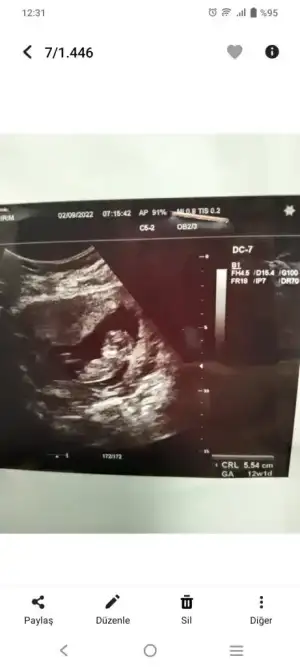

Arkadaşlar selam, benim de biraz araştırdığım bir konu ama daha önce yorumlayıp bir tecrübesi olan ve tahminleri tutan arkadaşlar 12 haftalık aşağıdaki görüntüyü yorumlayabilirler mi? Nub kısmı çok net görünüyor ama yorumlama konusunda destek rica ediyorum. Genelde çıkıntı yatay olunca kız, dikey olunca erkek deniyor. Bu görüntü yatay gibi ama uzun ve çıkık da olduğundan çok kararsız kaldım. Siz ne diyorsunuz?

Benim kızımın ultrason görüntüsüne öok benziyor 🙈 bi çok kişi erkek dedi ben kıza benzetmiştim. Sizinkini de kıza beenzettim. Rabbim sağlıkla kucağınıza almayı nasip etsin. Belli oldu mu cinsiyetiniz.